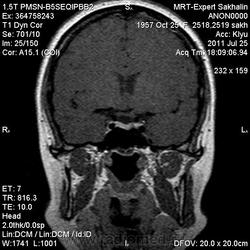

Как мы "динамичим"гипофиз

Женщина.6 лет назад выявлено образование левой доли нейрогипофиза.Пришла на контроль.

Постконтраст

Мне самой показался случай не совсем ясным, но динамик четко показывает участок с отставанием в контрастировании, воронка смещена вправо-о чем  думать бедному начинающему специалисту?